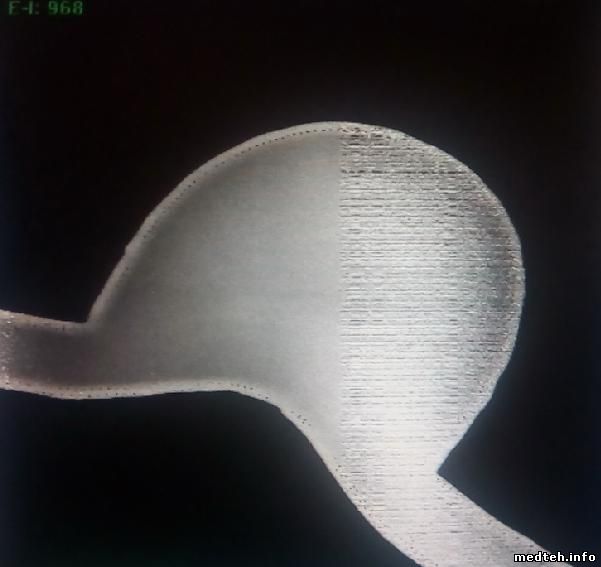

Присутствует два вида шума на рентгеновских снимках считанных с кассет сканером KODAK Point-Of-Care CR-140 - на всём снимке и на правой половине.

на половине снимка:

примечательно, что присутствует только 2 вида шума, но они не чередуются, а проявляются в случайном порядке.

вот ещё пара снимков с шумом по всей площади и на правой половине: